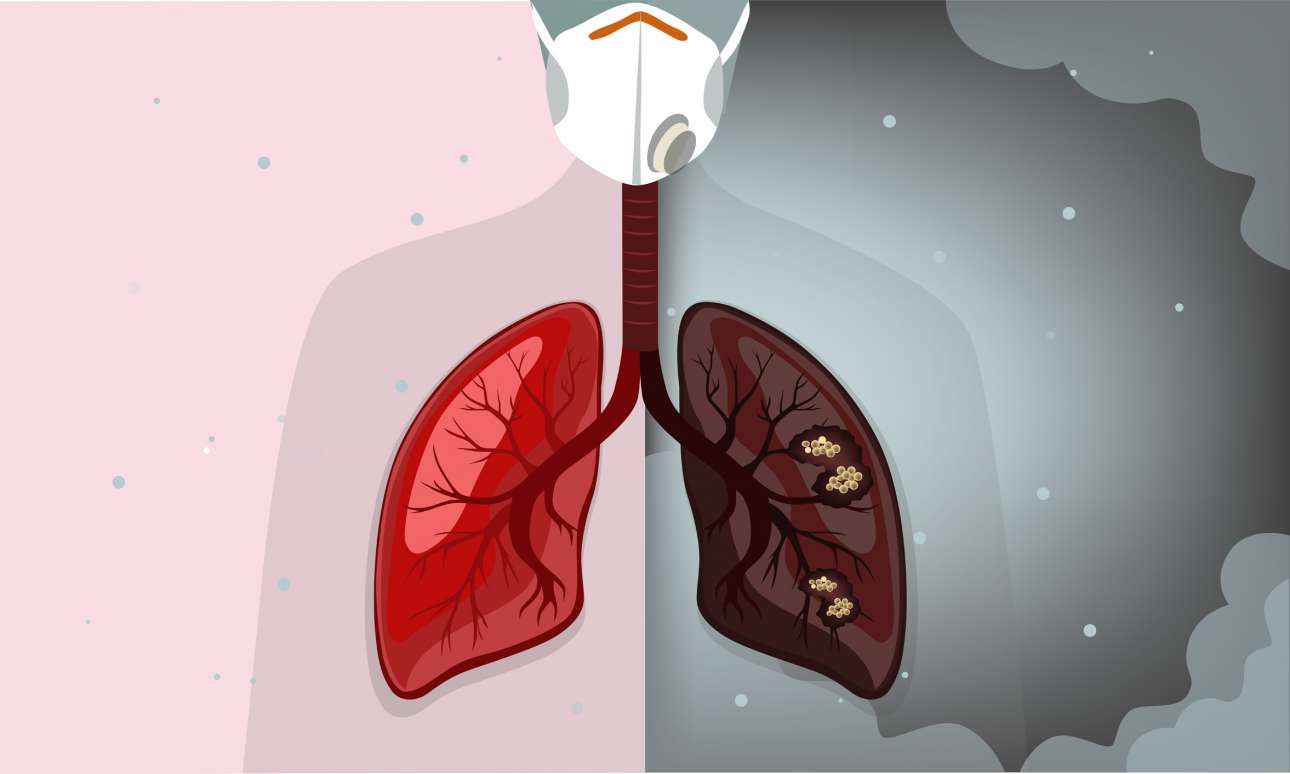

Πνεύμονες και καρδιά

Η συνέπειες του βρώμικου αέρα ξεκινούν με την εισπνοή του και φυσικά από τους πνεύμονες. Οι πνεύμονες προσβάλλονται από άσθμα, εμφύσημα και φυσικά από καρκίνο. Στην καρδιά αυξάνει τον κίνδυνο εμφράγματος, καθώς οι αρτηρίες που μεταφέρουν το αίμα στενεύουν και οι μύες αποδυναμώνονται.

Ενας από τους λόγους που επηρεάζει τόσο πολύ όλα τα όργανα του σώματος, είναι ότι τα μικροσωματίδια είναι τόσο μικρά, που μπορούν να εισχωρήσουν από τους πνεύμονες και να μεταφερθούν με το οξυγόνο σε όλο τον οργανισμό. Μελέτες που έχουν γίνει σε ζώα, δείχνουν ότι το οσφρητικό νεύρο μεταφέρει άμεσα στον εγκέφαλο τους ρύπους της ατμόσφαιρας. Επίσης, πολλές έρευνες έχουν δείξει ότι η ρύπανση επηρεάζει τη λειτουργία των γονιδίων.